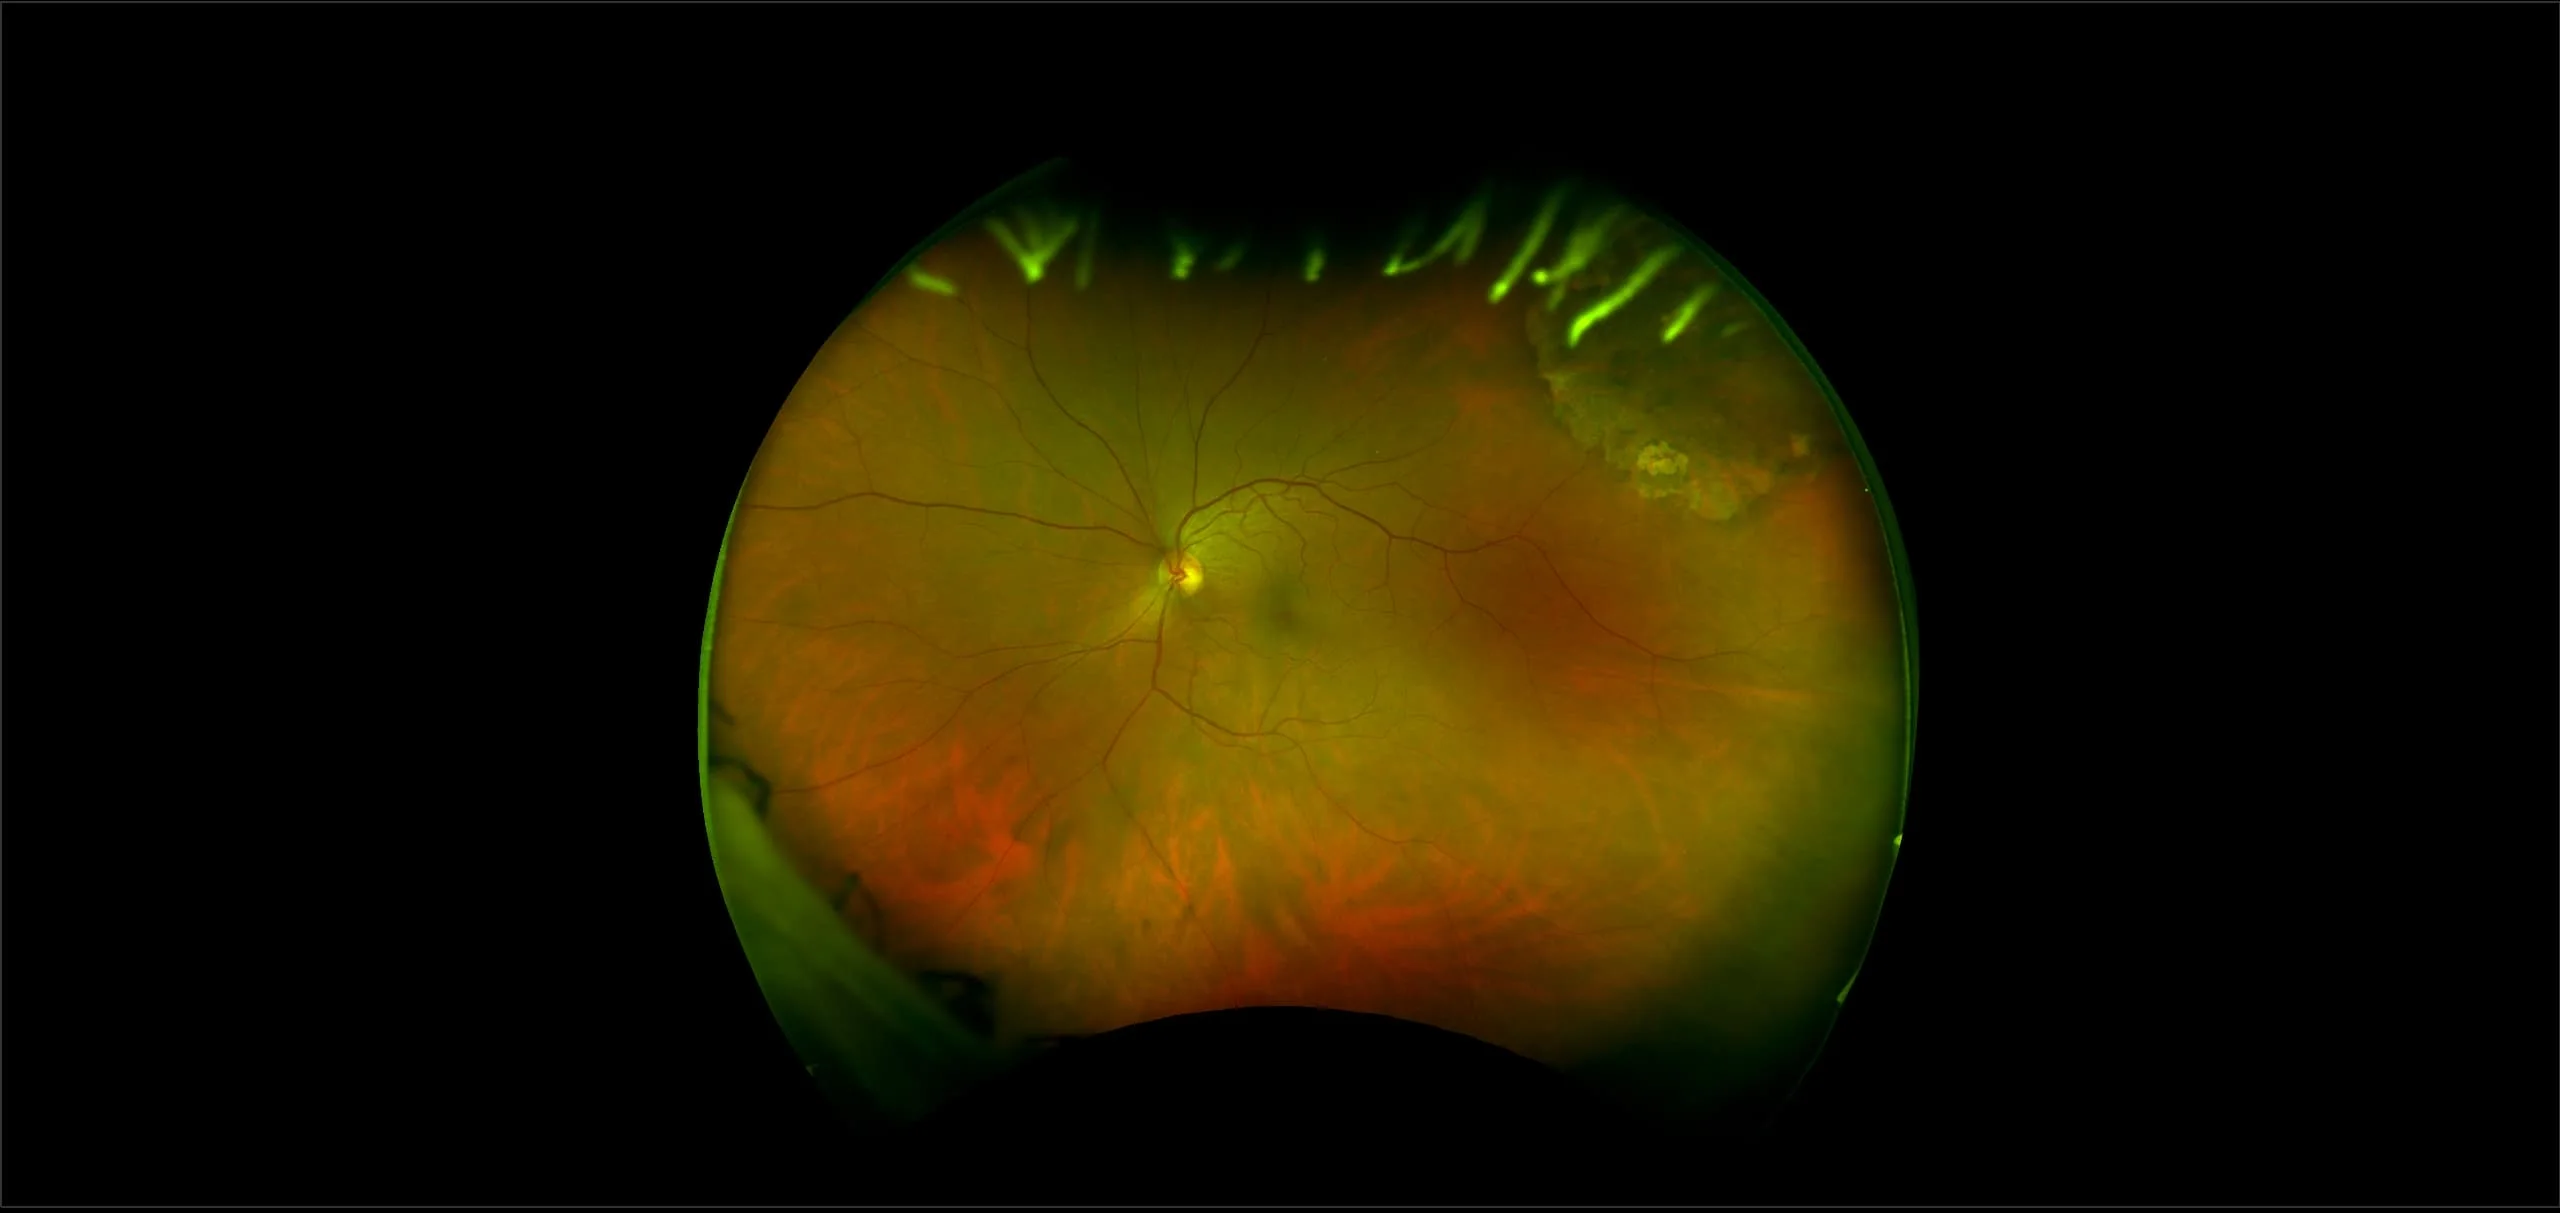

Retinal Atrophy

Retinal atrophy occurs when there is damage to the tissue in the retina that causes partial or total deterioration of your vision.